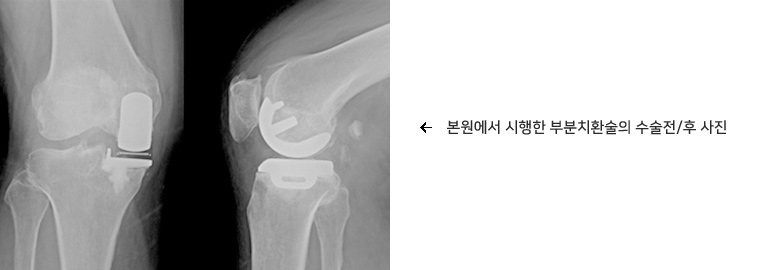

- 무릎 관절염

무릎 관절염